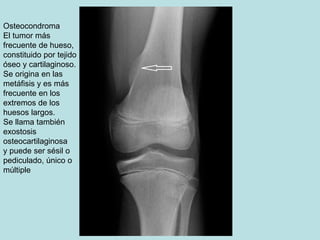

Osteocondroma

El tumor más

frecuente de hueso,

constituido por tejido

óseo y cartilaginoso.

Se origina en las

metáfisis y es más

frecuente en los

extremos de los

huesos largos.

Se llama también

exostosis

osteocartilaginosa

y puede ser sésil o

pediculado, único o

múltiple